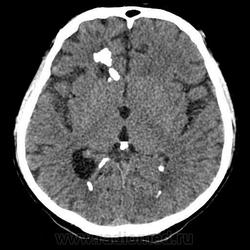

Parenchymal & sub-ependidymal calcifications, progressive hydrocephaly. Toxopolasmosis vs. CMV infection?

Да, Toxopolasmosis, Dr.Mario!

Сооветствующая клиника у неполучавшего ранее профилактические препараты ВИЧ-инфицированного пациента при множественном поражении головного мозга с типичной локализацией, положительный IgG. На фоне терапии противотоксоплазмозными препаратами клиническая положительная динамика. С иглой лезть с голову при такой картине смысла нет. В этом и верификация множественных паравентрикулярных и паренхиматозных кальцинатов головного мозга. У Вас, Андрей Юрьевич, по-другому?

Пациент находился на лечении в центре СПИДа, к нам попал после специфического лечения на реабилитацию в 2010 году. В данный момент клиника внутримозговой гипертензии.

При подозрении на токсоплазмоз, прежде чем прибегать к биопсии головного мозга, нужно назначить пробное лечение: если будет ответ на него, диагноз можно считать подтвержденным. В СМЖ обычно обнаруживается умеренный цитоз и немного повышенный уровень белка, однако если МРТ или КТ показали характерную картину (несколько очагов с усилением контраста) исследование СМЖ можно не проводить. Исследование СМЖ на токсоплазму с помощью ПЦР, по нашему опыту, себя не оправдывает, так как часто дает ложноотрицательные результаты.

Обязательно нужно провести серологическое исследование на токсоплазмоз. IgG антитела обнаруживаются у 97% больных церебральным токсоплазмозом, поэтому при отрицательном результате следует повторить исследование в другой лаборатории, и если отрицательный результат подтвердится, диагноз токсоплазмоза становится маловероятным. Ряд специалистов используют высокие и нарастающие титры IgG как диагностические критерии (Derouin, 1996), однако обоснованность такого подхода не доказана. IgM выявляются редко, поэтому исследование на эти антитела обычно бесполезно. Исследование крови с помощью ПЦР также имеет небольшое клиническое значение (обзор: Bretagne, 2003).